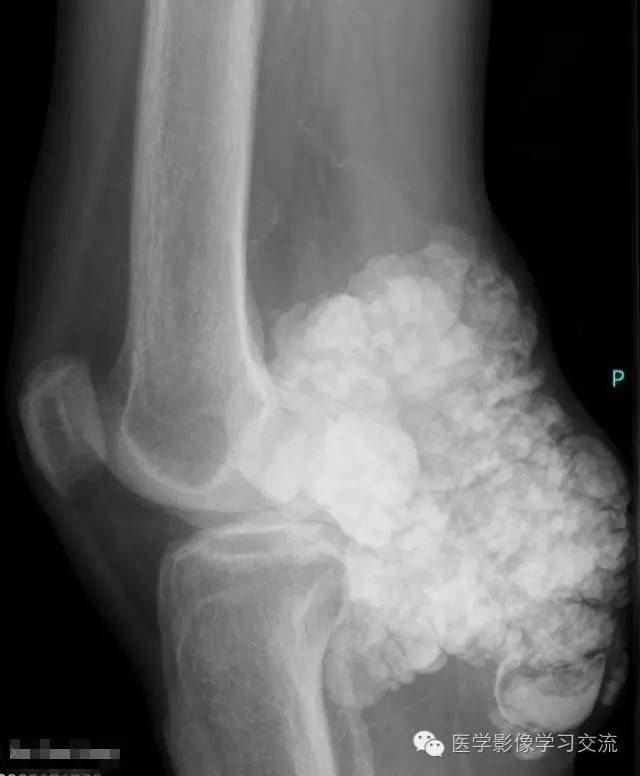

X线检查如下:

X 线检查是诊断 TC 的基本方法,其表现为关节旁关节伸侧软组织中,呈大小不一的钙化结节集结而成的分叶状团块,呈“卵石样” ,范围较广者可呈“流注状” ; 病变一般不累及邻近关节或骨骼。

CT 与X 线平片表现一致,但CT 对病变部位、形态及范围的显示更为全面,能清楚显示病变与邻近关节及骨骼的关系。